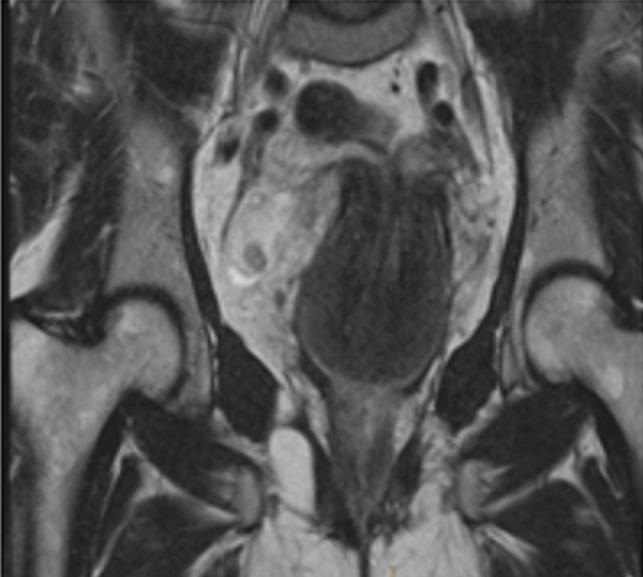

Uterine inversion is a rare postpartum complication. It is a rare condition in which the internal surface of the uterus protrudes through the vagina. Non-puerperal uterine inversion (NPUI) is extremely rare. In most instances, it is linked to uterine tumors. Among these tumors, leiomyoma is the most frequent cause reported in data. This condition may not be noticed until time of surgery. Malignancy is suspected in most cases. Nevertheless, uterine inversion can be diagnosed preoperatively using radiology. Difficulties in diagnosing NPUI makes this clinical case a challenge in gynaecology and not commonly reported in literature. We report our experience in the diagnosis and treatment of a complete non-puerperal uterine inversion associated with uterine angioleiomyoma. The patient's age was 44, gravida 2 para 1 presented with intermittent vaginal bleeding for four months and an acute abdominal cramping pain. On examination, a large mass lesion was observed which occupies the vaginal cavity and the contour of the uterine cervix could not be reached. Biopsies and Immunohistochemistry matched with an angioleiomyoma. She underwent a transvaginal surgical reposition technique: Spinelli's. It is important to diagnose accurate non-puerperal uterine inversion. Surgery provides good prognosis and it is necessary. We report a case of NPUI caused by angioleiomyoma. Nevertheless, malignancy must be eliminated in first place.

子宫内翻是一种罕见的产后并发症。它是一种罕见的情况,即子宫内部表面通过阴道突出。非产后性子宫内翻(NPUI)极为罕见。在大多数情况下,它与子宫肿瘤有关。在这些肿瘤中,平滑肌瘤是数据中最常见的报告原因。这种情况可能直到手术时才被发现。大多数情况下怀疑为恶性肿瘤。然而,放射学可用于术前诊断子宫内翻。NPUI 的诊断困难使得这种妇科临床病例成为一种挑战,并且在文献中并不常见。我们报告了我们在诊断和治疗与子宫血管平滑肌瘤相关的完全非产后性子宫内翻方面的经验。患者年龄为 44 岁,孕 2 产 1,间歇性阴道出血 4 个月,伴有急性腹痛。检查时,发现阴道腔内有一个大的肿块,触及不到子宫颈的轮廓。活检和免疫组织化学与血管平滑肌瘤相符。她接受了经阴道复位手术:Spinelli 技术。准确诊断非产后性子宫内翻非常重要。手术提供了良好的预后,这是必要的。我们报告了一例由血管平滑肌瘤引起的 NPUI。然而,首先必须排除恶性肿瘤。